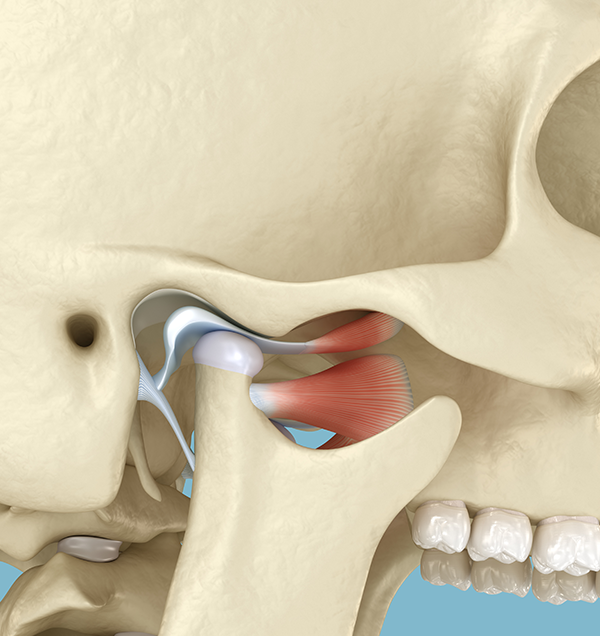

구강내과 X 교정 협진

교정이 필요한 환자들의 상당수는 턱관절 문제가 동반됩니다.

턱관절에 대한 면밀한 검사 없이 무턱대고 교정부터 한다면 교정의 결과가

좋지 못하거나 추후 심각한 턱관절 문제가 발생할 수 있습니다.

저희 치과에는 턱관절 전문가인 구강내과 전문의가

상주하고 있습니다.

세브란스 대학병원 출신의 턱관절&교정 원장 2인

함께 환자분의 턱관절을 면밀히 체크하며

완벽한 교정 결과를 만들어냅니다.

• 틀어진 턱을 바로잡는

턱 교정치료

턱관절의 위치를 변화시켜 턱이 정중앙에

놓일 수 있도록 서서히 유도하는 치료입니다.

• & 구강내과 & 교정전문의 협진